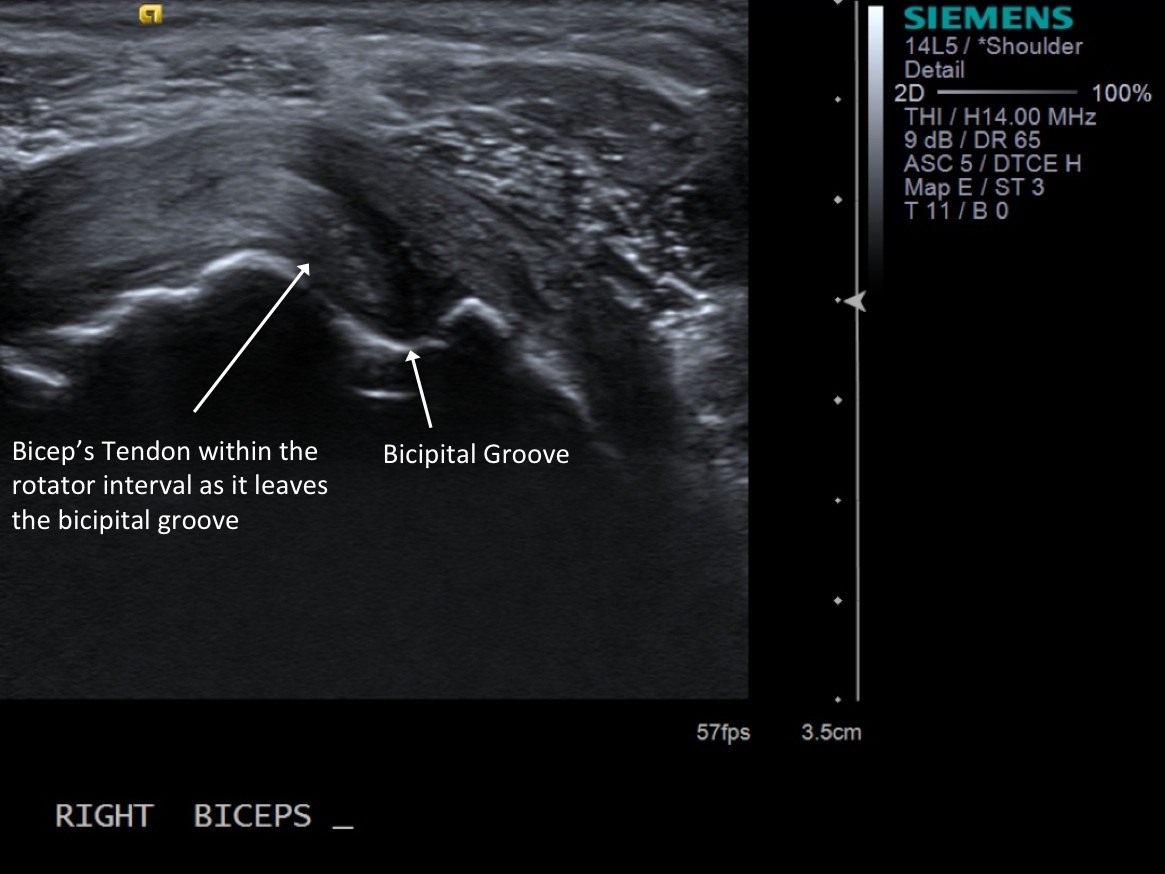

3. Scan patient looking at the biceps tendon (short axis/transverse) extra-articular and at the rotator interval. If there is fluid in the biceps tendon sheath when extra-articular, you can inject at that site. Otherwise, will need to inject at the rotator interval.

Extra-articular biceps tendon in transverse plane

Biceps Tendon in the Rotator Interval